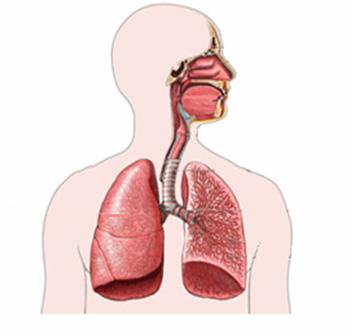

מערכת הנשימה

מערכת הנשימה מורכבת מדרכי האוויר העליונות, ודרכי האוויר התחתונות. דרכי האוויר העליונות כוללות את האף, הפה ותחילת קנה הנשימה ודרכי האוויר התחתונות כוללות את המשך קנה הנשימה, הסמפונות והריאות. בית החזה עצמו כולל גם את הצלעות (בין כל צלע- וריד, עורק, עצב), את עצם החזה(סטרנום) ואת השרירים הבין-צלעיים והסרעפת

איברי מערכת הנשימה ותפקידם

האף

הלוע

הקנה

הסימפונות

הריאות